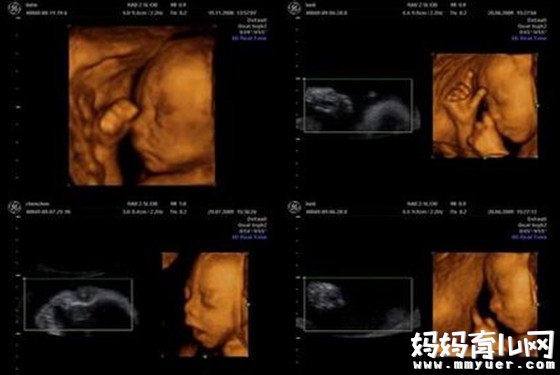

其实,三维彩超和四维彩超的区别主要在于在一个“时间维”,也就是说,三维彩超是图片,是静态的,四维彩超是录像,是动态的,可以让孕妈妈看到胎儿一连串的动作,所以四维看起来会更清楚明了,三维彩超只能是某个时间点上的照片,四维彩超的就可以做成DV那样连续的,可以刻录光盘。

三维彩超、四维彩超的图像则是后期生成的,并不是说观察到的图像就是三维、四维的,而是仍然用普通彩超观察,然后通过仪器中的转换软件将观察到的平面图像转成三维、四维的立体图像,说得更直白一点,如果将你的家用电脑中装上类似软件,你就可以把普通B超的图像自己在家里转换成立体的了。

在诊断的意义上,三维彩超、四维彩超没有任何对诊断更有利的地方,只不过是不懂得B超图像的人也能看出模样而已。它们的意义也就在于,您能看见宝宝还在肚子里的模样了。

四维彩超可立体显示胎儿的颜色、面、各器官的发育情况,甚至胎儿在母体里的状态也可以观察到;对胎儿畸形,如唇裂、腭裂、骨骼发育异常、心血管畸形等能早期诊断。